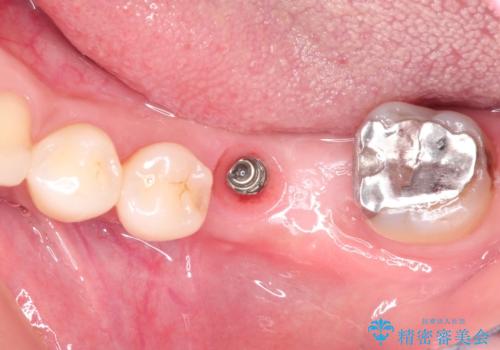

インプラントの種類:strauman SLActive

- 外科手術のため、術後に痛みや腫れ、違和感を伴います

- メンテナンスを怠ったり喫煙により、お口の中に大きな悪影響を及ぼすインプラント周囲炎等にかかる可能性があります